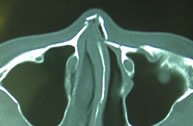

鼻骨骨折 (はなの骨折)

鼻骨の骨折は顔面骨の骨折の中で最も多い骨折です。受傷してから2~3週間以内であれば皮膚に傷つけずに治療することが可能です。原則的には、入院して全身麻酔による治療を行います。当科では、骨折の整復の状況(治り具合)を手術中に超音波診断装置を用いて評価することで、正確な治療を行っています。整復後は、鼻腔内にガーゼを詰めて、外側はプラスチック樹脂製のガードで固定を行います。受傷から1ヶ月以上経過した陳旧性では骨を切って整復する必要があります。その場合も鼻腔内の切開から行い表面には傷をつけずに行いますが、骨移植などを要することもあります。

| 鼻骨骨折CT像(整復前) | 鼻骨骨折CT像(整復後) |